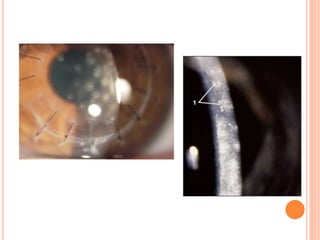

S/P DALK FOR KERATOCONUS IN 7YR CHILD

S/P DALK 1 WEEK POSTOP